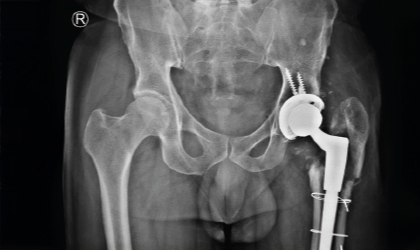

Cancer, Hips, Triumph

This is one of the youngest girls I have done a hip replacement in. Her right hip was replaced at the age of 13,